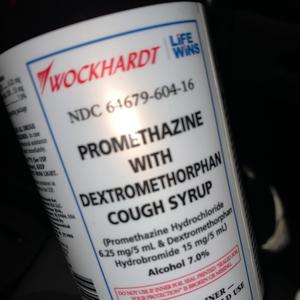

OD CRASHING (feat. Jblack3kk & Yungbg3x)

BabyRackz, Jblack3kk, Yungbg3x